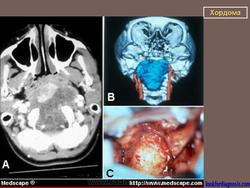

Хотя хордома может возникнуть в любом отделе позвоночного столба, наиболее излюбленными местами локализации этой опухоли являются 1-й шейный позвонок и пояснично-крестцовый отдел позвоночника. Это достаточно редкое заболевание. Чаще всего хордома возникает у мужчин среднего возраста. По данным рентгенографии, компьютерной томографии, магнитно-резонансной томографии можно поставить только предварительный диагноз. Для подтверждения диагноза необходимо проведение биопсии (забор кусочка опухолевой ткани с проведением микроскопического исследования). Лечение хирургическое. Прогноз зависит от размеров опухоли, наличия осложнений и общего состояния пациента.

Хордома развивается из персистирующих остатков хорды. Преимущественная локализация хордомы - это область сфеноокципитального сочленения и крестцово-копчиковый отдел позвоночника. Сведения о частоте отдельных форм хордомы весьма разноречивы.

Рентгенологическая картина хордом характеризуется наличием очага деструкции, захватывающего ряд позвонков. Костный дефект представляется однородным, либо крупнокамерным за счет тонких костных полосок. Показаны боковые рентгенограммы крестца, на которых при хордоме определяется увеличение передне-заднего размера крестца за счет экспансивного роста опухоли. В отдельных случаях в опухоли прослеживаются небольшие костные включения, которые могут служить поводом для ошибочной диагностики тератом, особенно в детском возрасте. (В детском возрасте тератомы встречаются часто, их соотношение с хордомами, по данным М. В. Волкова, 60:2).

Крестцово-копчиковая хордома.